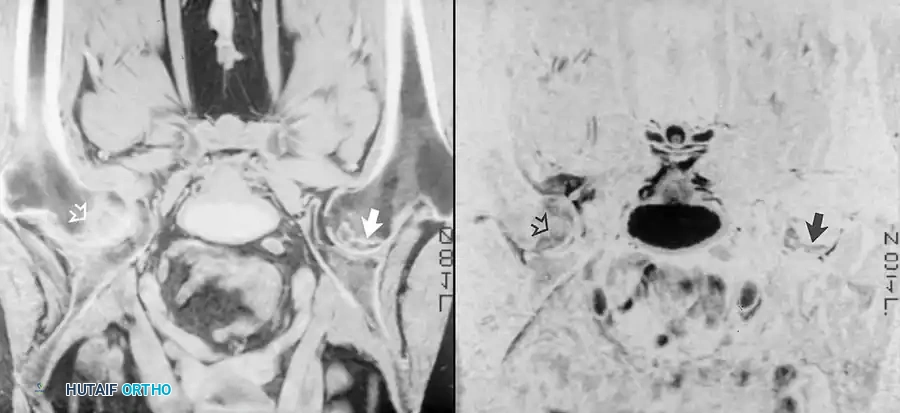

عادة ما يتم إجراء تسلسلات الصدى المغزلي في المستويات المحورية والإكليلية. كما يجب الحصول على صور سهمية عند التحقيق في تنخر العظام. تظهر الصور الموزونة بالزمن الأول مظهرا كلاسيكيا لتنخر العظام يتمثل في منطقة جغرافية ذات إشارة نخاع منخفضة داخل الدهون الساطعة الطبيعية لرأس الفخذ. غالبا ما تُحاط هذه المنطقة غير الطبيعية بشريط منخفض الإشارة يمثل العظم الإقفاري. وتكشف الصور الموزونة بالزمن الثاني عن شريط داخلي ثان من الإشارة الساطعة، ويُطلق على هذا المظهر اسم علامة الخط المزدوج، وهي علامة تشخيصية أساسية لتنخر العظام.

في حالات هشاشة العظام العابرة، تُظهر تسلسلات الزمن الأول وذمة منتشرة كإشارة منخفضة نسبيا مقارنة بالنخاع الدهني الخلفي. تصبح هذه الوذمة شديدة السطوع في سلسلة الزمن الثاني وتبرز أكثر عند استخدام تقنيات قمع الدهون. يُطلق على مظهر النخاع هذا اسم نمط وذمة نخاع العظم.